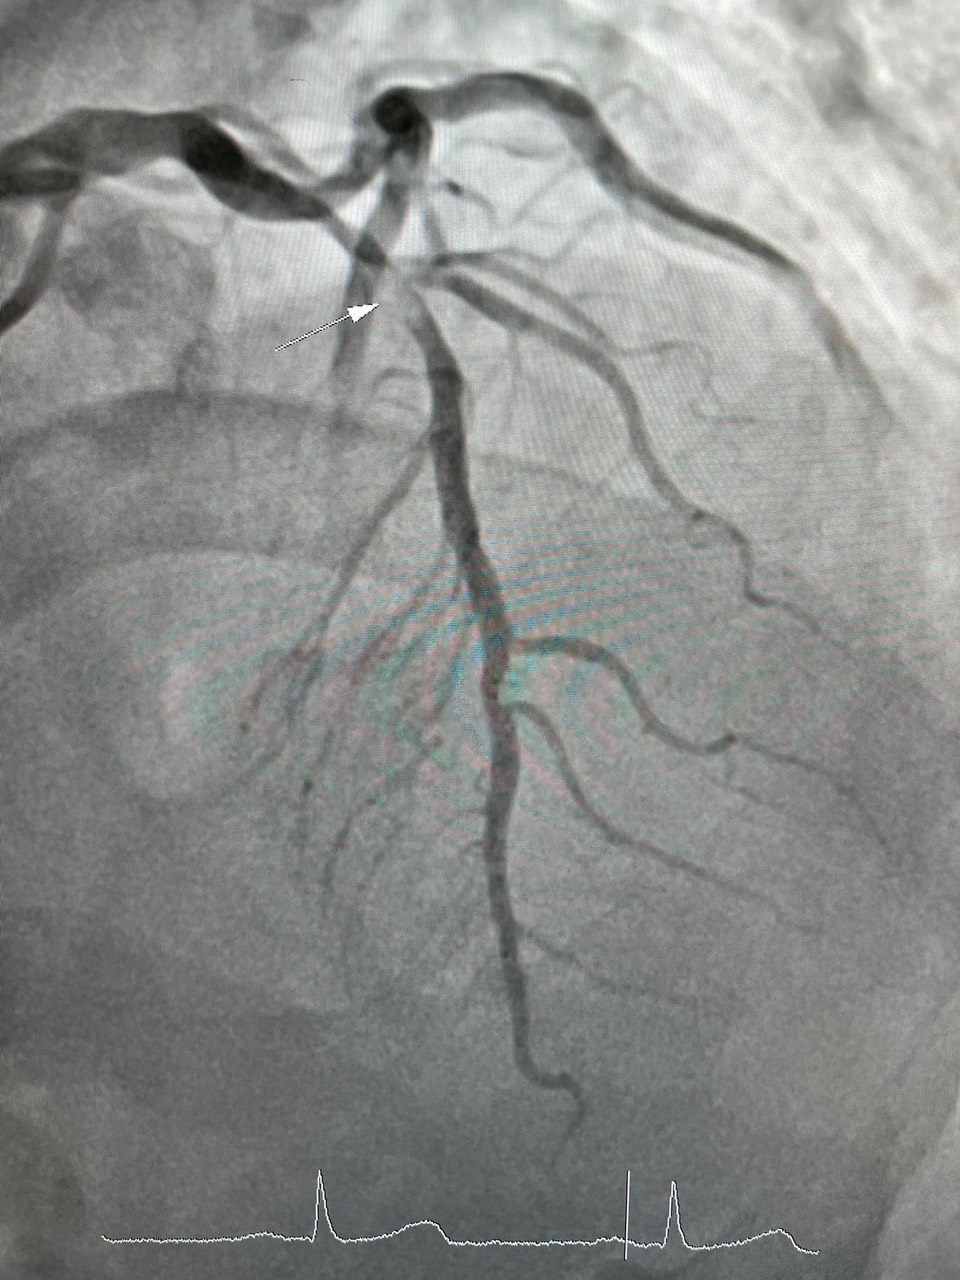

Ngày 17 tháng 5 năm 2022, Bệnh viện đa khoa tỉnh Hòa Bình tiếp nhận bệnh nhân nam, 62 tuổi, nhập khoa Hồi sức cấp cứu trong tình trạng đau dữ dội vùng ngực trái, đau như bóp nghẹt vùng sau xương ức, đau lan lên cằm và lan ra cánh tay trái. Ngoài ra, bệnh nhân rơi vào tình trạng tím tái toàn thân, vã mồ hôi, chân tay lạnh, mạch đập chậm khoảng 52 lần/phút, huyết áp 90/60mmHg. Qua thăm khám lâm sàng và một số xét nghiệm cận lâm sàng, bệnh nhân được chẩn đoán Nhồi máu cơ tim cấp (tắc mạch máu cung cấp máu cho tim). Bệnh nhân được chuyển ngay đến khoa Nội Tim mạch để chụp mạch vành cấp cứu, kết quả: huyết khối gây hẹp 95% đoạn I-II động mạch liên thất trước, hẹp 90% đoạn I động mạch vành bên phải. Kíp can thiệp động mạch vành đã tiến hành nong và đặt Stent đoạn I động mạch liên thất trước và đoạn I động mạch vành bên phải. Sau can thiệp động mạch vành của bệnh nhân được tái thông hoàn toàn, bệnh nhân hết đau ngực, huyết động ổn định. Sau 6 ngày điều trị sức khoẻ người bệnh ổn định hết đau thắt ngực.

(Hình 1: huyết khối gây hẹp 95% động mạch liên thất trước. Hình 2: sau nong và đặt Stent động mạch liên thất trước tái thông hoàn toàn)